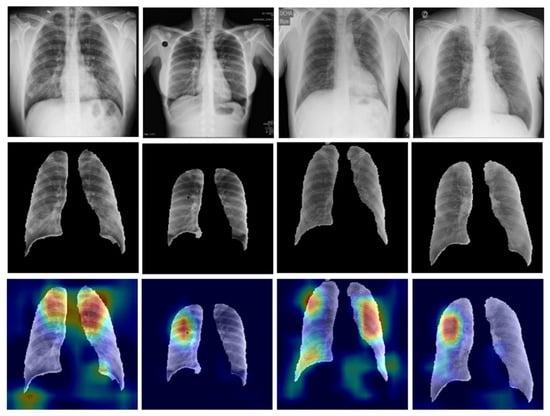

3.1.6. Segmentation of the Classification Dataset

3.2.3. Heatmap Visualization: An Explainable AI Model